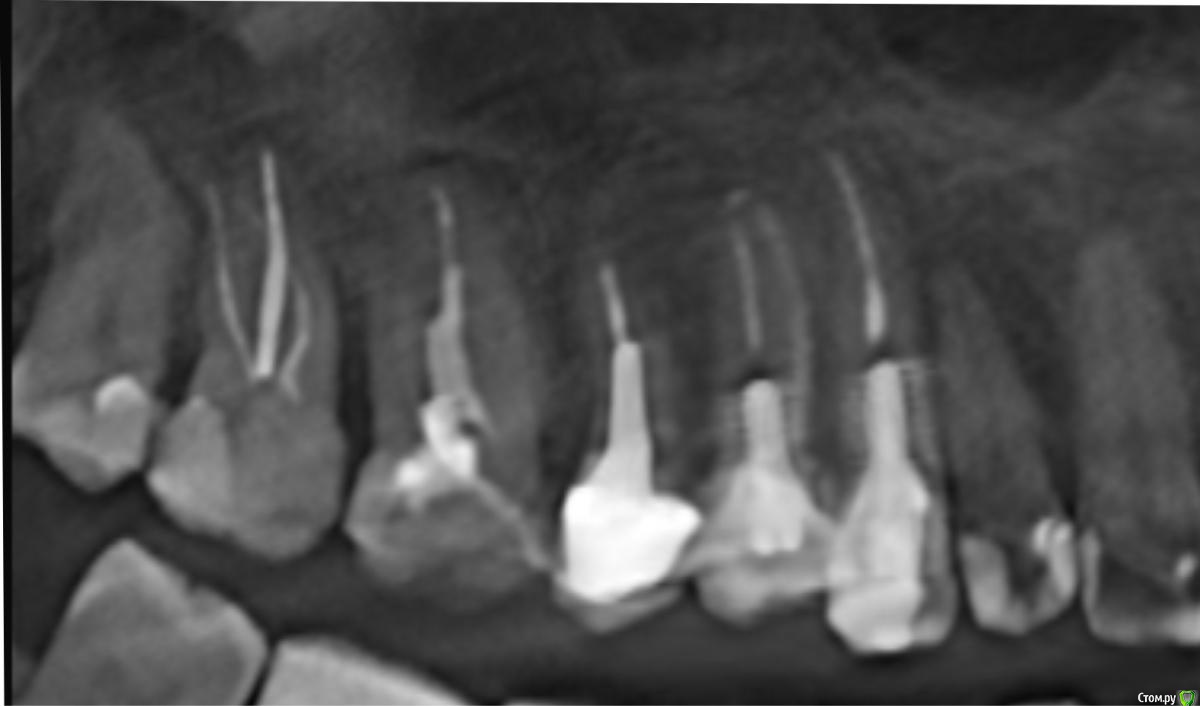

стихия Опубликовано 20 мая, 2018 Поделиться Опубликовано 20 мая, 2018 Здравствуйте, уважаемые стоматологи. Прошу вашего совета вот по такому вопросу. Лет 15 назад у меня были лечены правые верхние 3-й и 4-й зубы. Были запломбированы каналы и в каждый зуб вкручен анкер. Зубы с того времени не беспокоят, стоят надежно. Но есть одна проблема: со временем они стали просто отвратительного серо-желтого цвета и эстетически это выглядит мягко скажем не очень красиво. Несколько раз обращалась к врачам с просьбой что-то сделать с этими зубами, как-то их отбелить, наклеить винир или коронку на крайний случай - все отказывались (( Говорят, выкручивать анкера в моем случае не безопасно, можно разломать корни. Отбеливать тоже отказывались, говорили не поможет, т.к. от самих зубов мало что осталось. И вот недавно, попала я к одному врачу, который сказал, что переделает мне эти зубы. Снимет анкера, поставит стекловолокно, отбелит, нарастит. Я конечно очень обрадовалась и согласилась, но немного побаиваюсь и сомневаюсь: стоит ли их все-таки трогать, может действительно есть большая вероятность, что корни расколются и тогда только удаление... Посмотрите, пожалуйста, мои снимки, и подскажите, есть ли шансы эти зубы переделать и привести в нормальный вид, или лучше не трогать? И если анкера достанут, может лучше сразу коронки одевать? Пы.Сы. каналы в этих зубах вероятнее всего распломбировать не удастся... был аналогичный зуб слева (лечен тем же доктором в то же время) - пришлось удалить из-за кисты, канал не прошли. Ссылка на комментарий

red_butler Опубликовано 20 мая, 2018 Поделиться Опубликовано 20 мая, 2018 при грамотном подходе анкера легко и безопасно извлекаются Ссылка на комментарий

St. Опубликовано 20 мая, 2018 Поделиться Опубликовано 20 мая, 2018 при грамотном подходе анкера легко и безопасно извлекаются+1А коронки будут наиболее надежным и эстетичным вариантом восстановления Ссылка на комментарий